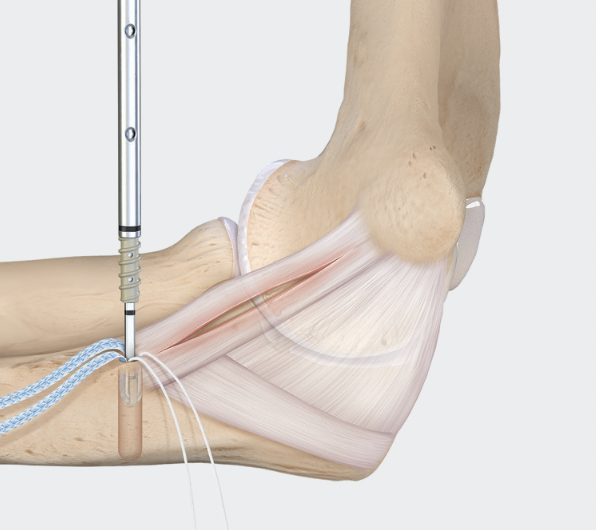

Docking technique

Technique

Vumedi UCL reconstruction with palmaris longus and docking technique video

Arthroscopy techniques UCL reconstruction with palmaris longus and docking technique PDF

Distal insertion - transverse tunnel across ulna / sublime tubercle

Proximal insertion - blind tunnel in medial epicondyle